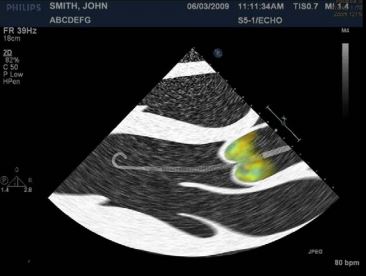

@AHajduczok @Texas_Heart Correct positioning can also be confirmed through color doppler.

If the catheter is positioned properly, you would expect turbulent flow above the aortic valve (indicating the outlet is above the valve)